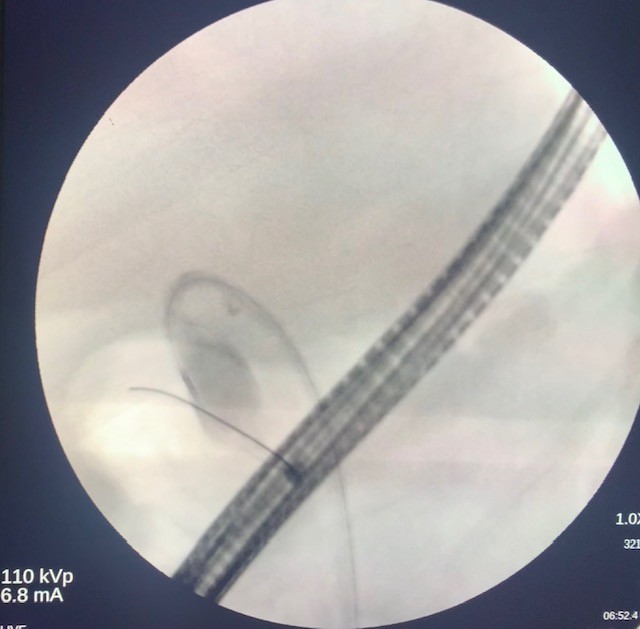

The gastroscope (Olympus, America) was passed into the esophagus under direct visualization. The esophageal and gastroesophageal junction appeared fine without inflammation or lesions. Examination of the stomach showed portal hypertension gastropathy without gastric varices. The duodenal bulb and second part of the duodenum were also clear without pathology. Next, the linear array echoendoscope (Olympus) was passed into the esophagus and advanced into the stomach. EUS imaging revealed a cirrhotic liver surrounded by a large amount of ascites (Fig 1). From the duodenum, the gallbladder was assessed and demonstrated signs of gallbladder wall thickening with a large burden of sludge and small stones (Fig 2).

Figure 2. EUS visualization of the gallbladder with stones and a build-up of biliary sludge.

Figure 2